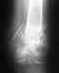

Перелом ноги и раздробление позвонков

Просим помощи в консультации. Оперировать будут в городе Златоуст, Челябинской обл. Что можно сделать в нашем случае. Прикрепляю снимок